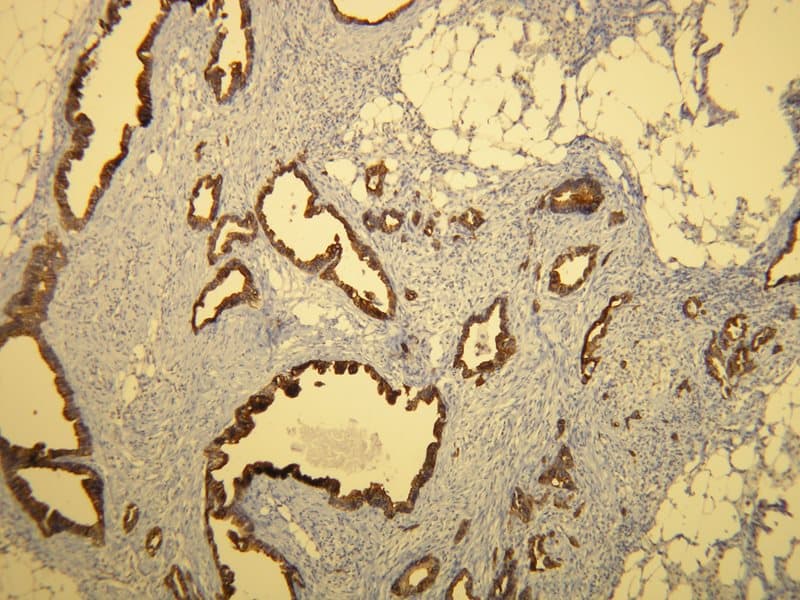

Adenocarcinoma ductal de páncreas |

Las citoqueratinas son proteínas estructurales de filamentos intermedios que forman el citoesqueleto de las células epiteliales, contribuyendo a la estabilidad mecánica, la integridad celular y la arquitectura tisular. La citoqueratina 7 (CK7), una citoqueratina de tipo II, se expresa en muchos epitelios glandulares y ductales, incluidos los conductos biliares, los conductos pancreáticos y porciones de la mucosa gástrica y del intestino delgado. En contraste, la mucosa colónica normal es típicamente CK7-negativa, lo que convierte a esta proteína en un marcador de referencia útil en la patología gastrointestinal (GI).

Se ha observado una expresión aberrante de CK7 en subgrupos de neoplasias gastrointestinales, incluidos algunos adenocarcinomas colorrectales, gástricos y de intestino delgado. En estos contextos, la inmunoreactividad de CK7 puede reflejar alteraciones en la diferenciación epitelial y la linaje celular. En ciertos estudios, los carcinomas colorrectales CK7-positivos se han asociado con características histológicas mucinosas o de alto grado. Aunque la CK7 no es universalmente pronóstica, su expresión proporciona información sobre la biología tumoral y puede ayudar a caracterizar subtipos histopatológicos.